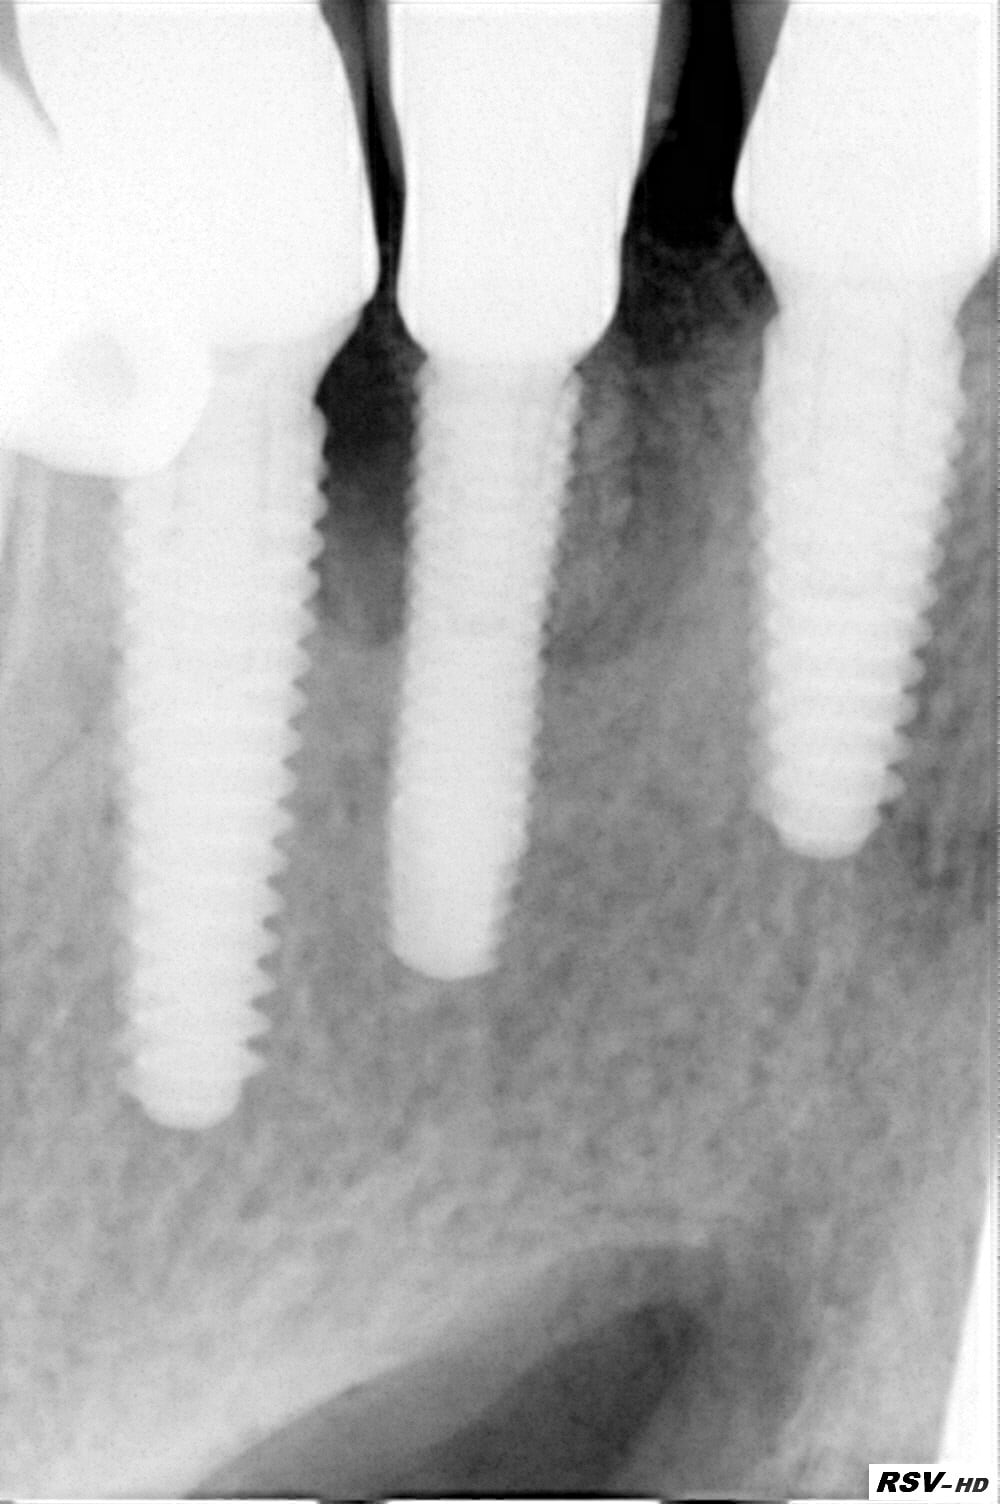

Je dirais pour le prix plus près de 300€, enfin très très cher car ils veulent se positionner en premium. Je sais j'y ai cru jusqu'à ce que les fractures arrivent.....fracture d'implant!

J'ai cru à une péri implantite quelle surprise ! Merci Megagen.....et quand je leur en ai parlé évidemment je suis le seul!....MDR Si je rajoute le SAV purée je suis largement perdant.

Voici un cas de molaire (le 1er) . Cela prouve que la taille de l'implant n'est pas la cause.

Dr Marcus pour la molaire avec un « core » de 3,3 de diamètre (sans compter les spires) ça ne m’étonne qu’à moitié la fracture

Non là core de 4.8!!!

ce qui m’a toujours interpellé c’est que pour du 5 ou du 5,5 le core soit de 3,3 autrement dit très fragile.

Si ça casse à 4,8 effectivement y a comme qui dirait un problème :)

Ce sont des implants en titane grade 4. Je me suis laissé séduire oubliant les principes mécaniques les plus élémentaires.

Dans ce cas la ténacité et la ductibilité sont très faibles. Finalement ce n'est que chance de ne pas avoir plus de problème.